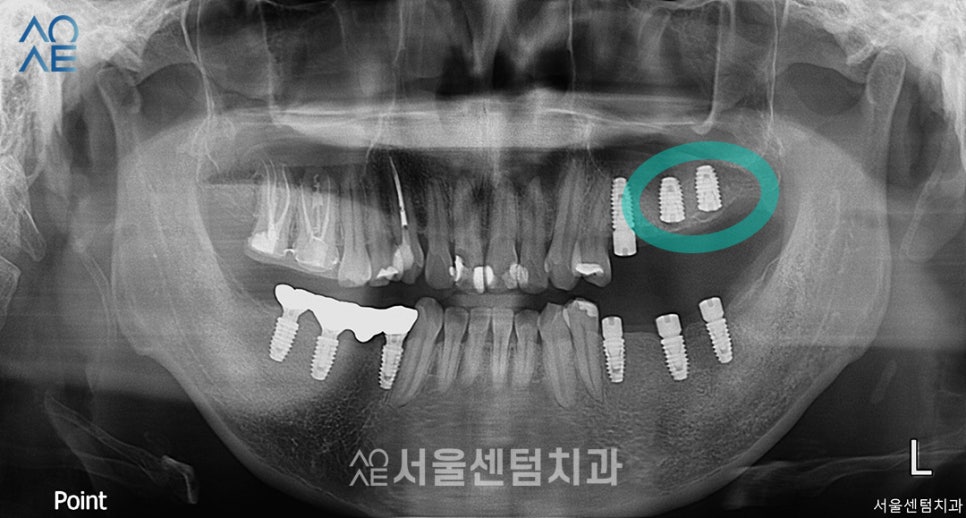

그 다음으로는 오른쪽 아래 어금니에

총 3개의 임플란트를 식립 후

찍은 엑스레이사진입니다.

임플란트는 1차 2차 수술로 나뉘는데

이 분의 경우에는 2차 수술이 필요 없는

일체형으로 식립하였습니다.

2차수술에서는 임플란트의 뿌리를 노출시키는데

일체형의 경우에는 이 과정이 필요 없습니다.

따라서 잇몸이 충분히 아무는 시간을 가진 후

바로 인상채득을 진행하면 됩니다.